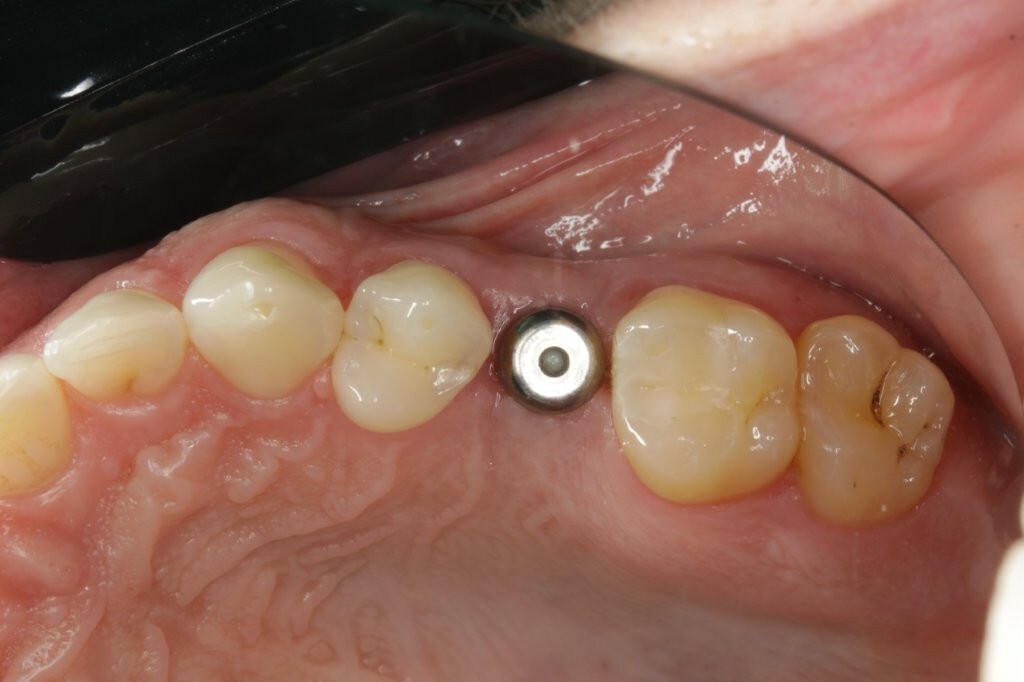

Zu Beginn wurde das Einzelzahnimplantat (Conelog ScrewLine Titanimplantat, 3,8 x 9,0 mm, Camlog) in Regio 25 gesetzt, geschlossen eingeheilt und nach Freilegung mit einem Gingivaformer (Conelog Gingivaformer, wide body, 3,8 x 6,0 mm, Camlog) versehen (Abb. 3). Mithilfe eines VITA-Farbschlüssels (VITA Zahnfabrik) wurde für die spätere Krone die Farbe A3 bestimmt (Abb. 4).